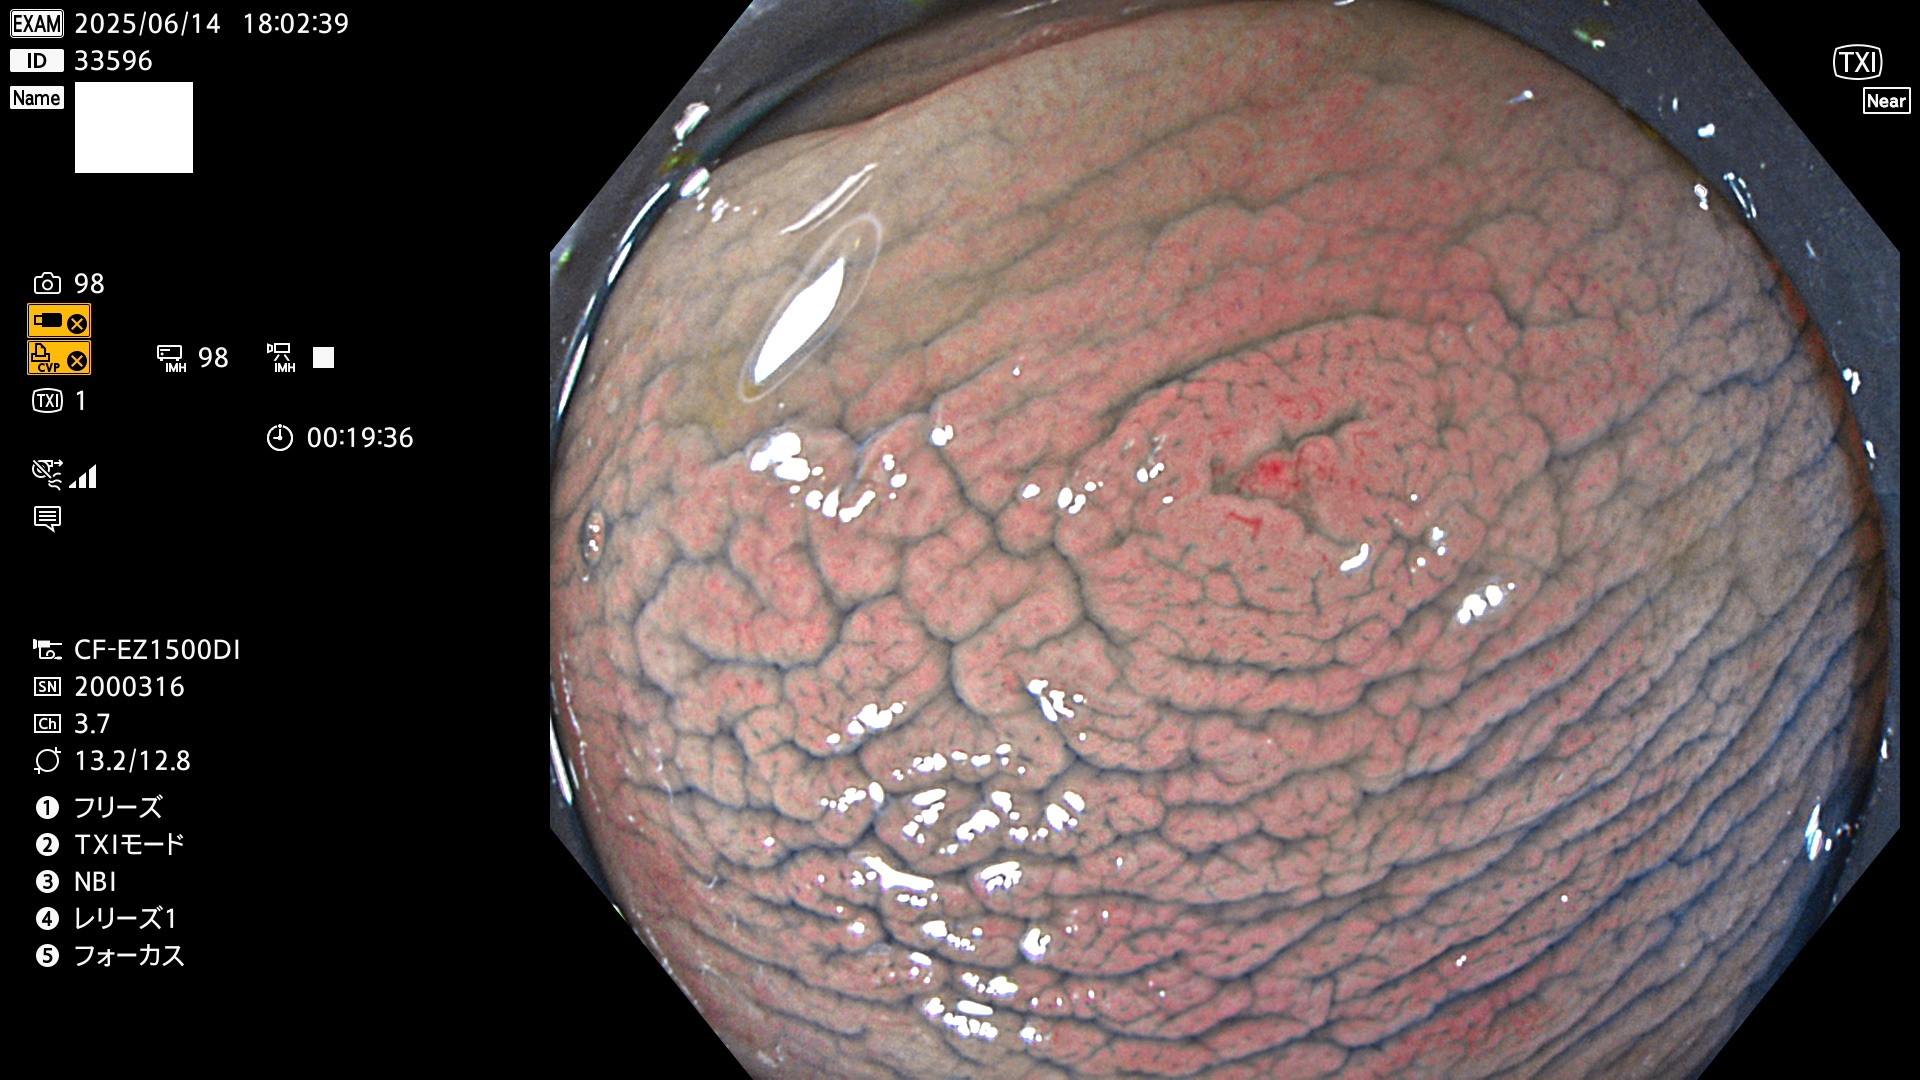

完全に平坦な物をUb、陥凹している物をUcと呼びます。Ubは認識が困難で、Ucはびらん(炎症)と紛らわしいために見落とされやすく、「内視鏡後・大腸癌」の原因になります。

抽出の対象期間 2025年6月12日〜6月15日の4日間(48件の検査)14個 (14/48=29%)